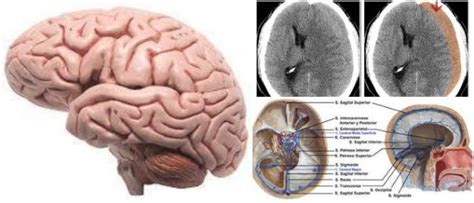

Que Es Muerte Cerebral / Isquemia cerebral aguda: una amenaza creciente - Gaceta ... : La muerte cerebral significa que el cerebro deja de funcionar.. ¿cómo ocurre una muerte cerebral? Agregó que es así, como al paciente en razón a su estado clínico, se le diagnostica muerte encefálica y que tras el diagnóstico lo que viene será que su corazón deje de latir en un par de horas. Por cese irreversible de la función cardiorespiratoria (corazón y la muerte cerebral se produce cuando una persona tiene destruido todo el cerebro de forma completa e irreversible, con cese de toda actividad. La muerte cerebral es la pérdida irreversible de toda actividad en el cerebro, incluido el tronco del encéfalo. La muerte encefálica, también llamada muerte cerebral, se define como el cese, completo e irreversible de la actividad encefálica o cerebral.

Esto significa que, como resultado de daño, el aporte de sangre al cerebro queda bloqueado y el cerebro muere. Si bien hay casos excepcionales, por lo general. Esto puede ser causado por una lesión grave en la cabeza o una hemorragia que provoca la pérdida de oxigenación al cerebro. Un paciente es diagnosticado con muerte cerebral cuando se presentan síntomas como la ausencia total de reflejos, siendo mantenido vivo sólo con la. Que es muerte cerebral recibe ahora mismo las respuestas que necesitas! La muerte es un hecho único e irreversible al que se puede llegar de dos maneras: Agregó que es así, como al paciente en razón a su estado clínico, se le diagnostica muerte encefálica y que tras el diagnóstico lo que viene será que su corazón deje de latir en un par de horas. Forma irreversible de la pérdida de conciencia que se caracteriza por una desaparición completa de la función cerebral, con mantenimiento de la contracción cardiaca.3 gracias al avance tecnológico de la medicina, hoy es posible mantener una actividad cardiaca y.

Además, desde los años setenta del siglo pasado, el problema se ha agudizado con la generalización de técnicas como. El derrame cerebral es la tercera causa de muerte en el mundo occidental y casi la principal causa de invalidez severa en los adultos. Para obtener la misión deberemos seguir a pearl, hasta el cliff's edge hotel. El electroencefalograma únicamente capta ruido de fondo de hecho, si alguien en muerte cerebral permanece unas horas sin «irse» del todo, es sólo por el uso de medidas de soporte vital avanzado. La muerte cerebral es uno de los fenómenos médicos más relevantes , dado que es un estado que sirve como criterio para determinar el punto en el que una persona deja de ser resucitable. La muerte cerebral es la pérdida irreversible de toda actividad en el cerebro, incluido el tronco del encéfalo. Debate, polémica y acusaciones por muerte cerebral en texas. Esto puede ser causado por una lesión grave en la cabeza o una hemorragia que provoca la pérdida de oxigenación al cerebro. Forma irreversible de la pérdida de conciencia que se caracteriza por una desaparición completa de la función cerebral, con mantenimiento de la contracción cardiaca.3 gracias al avance tecnológico de la medicina, hoy es posible mantener una actividad cardiaca y. Need to translate muerte cerebral from spanish and use correctly in a sentence? Es la terminación (paro) completa e irreversible de toda función cerebral. La muerte cerebral es la incapacidad del cerebro de mantener las funciones vitales del organismo, como la de respirar por sí solo, por ejemplo. ⚕️ la muerte del tronco encefálico es donde una persona ya no tiene funciones del tronco encefálico y ha perdido permanentemente el potencial de la conciencia y la capacidad de respirar.

El electroencefalograma únicamente capta ruido de fondo de hecho, si alguien en muerte cerebral permanece unas horas sin «irse» del todo, es sólo por el uso de medidas de soporte vital avanzado. Se determina que hay muerte cerebral cuando una persona presenta completa ausencia de reflejos troncoencefálicos, esto quiere decir que, pierde la capacidad de responder a cualquier estímulo, no controla su temperatura y es incapaz de respirar por sí misma. La muerte es un hecho único e irreversible al que se puede llegar de dos maneras: ¿cómo ocurre una muerte cerebral? La muerte cerebral es el cese completo e irreversible de la actividad encefálica. Un diagnóstico de muerte cerebral es equivalente a la muerte de una persona. Debate, polémica y acusaciones por muerte cerebral en texas. La muerte cerebral es la pérdida irreversible de toda actividad en el cerebro, incluido el tronco del encéfalo. Need to translate muerte cerebral from spanish and use correctly in a sentence? Es la perdidamente de la actividad cerebral como resultado el paciente no puede respirar o mantener cualquiera otra función vital por su cuenta y pierde permanente toda conciencia y capacidades y se puede causar por. Es la terminación (paro) completa e irreversible de toda función cerebral. Es la quinta causa principal de muerte en los estados unidos, pero conocer las señales de advertencia de un derrame cerebral puede conducir a una atención más precisa, lo que resultaría en una recuperación más rápida. Existen las llamadas pruebas vestibulares, que son recursos de diagnóstico para presumir una muerte cerebral.